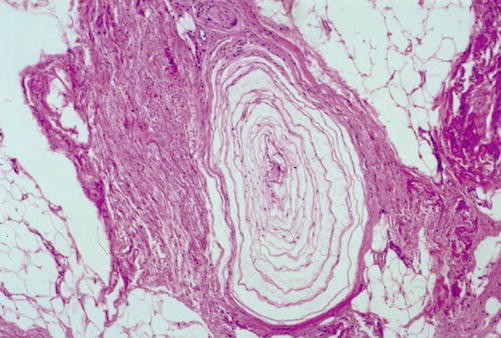

Morton Neuroma Pathology

Morton Neuroma Pathology / Troy watson, m.d., serving henderson nv, las vegas nv and the surrounding area.